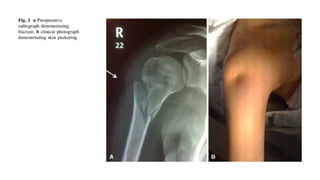

Proximal Humerus Fractures

Epidemiology

● Most common fracture of the humerus

● Higher incidence in the elderly, related to

osteoporosis

● Female to Male ratio 2:1

Mechanism of Injury

● Most commonly a fall onto an

outstretched arm from standing height

● Young patients typically present after a